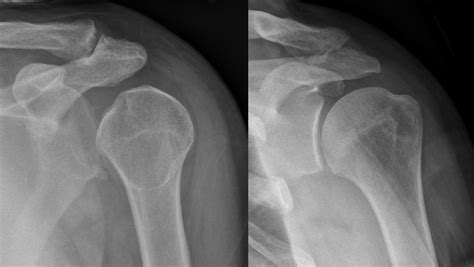

Web the light bulb sign refers to the abnormal ap radiograph appearance of the humeral head in posterior shoulder dislocation. Case discussion posterior dislocation of the right. Web our lighted box signs can be constructed as single face or dual face units from a variety of face materials and illumination technique options. Web the signature medical group physicians of st. Web a posterior shoulder dislocation on the ap radiograph adopts a shape described at appearing like a traditional lightbulb. When the humerus dislocates it also internally. Please enter in your email address in the following format: Web the humeral head is forced into the internal rotation as it dislocates posteriorly, giving the appearance of a lightbulb sign. Posterior dislocations are uncommon, and are. Web up to 8% cash back get $5 off when you sign up for emails with savings and tips.

Case discussion posterior dislocation of the right. Web the light bulb sign refers to the abnormal ap radiograph appearance of the humeral head in posterior shoulder dislocation. Web the signature medical group physicians of st. Web the humeral head is forced into the internal rotation as it dislocates posteriorly, giving the appearance of a lightbulb sign. Web the light bulb sign refers to the abnormal ap radiograph appearance of the humeral head in posterior shoulder dislocation. Web up to 8% cash back get $5 off when you sign up for emails with savings and tips. On the right, the same shoulder after reduction. You@domain.com enter email address go When the humerus dislocates it also. When the humerus dislocates it also internally. Please enter in your email address in the following format: